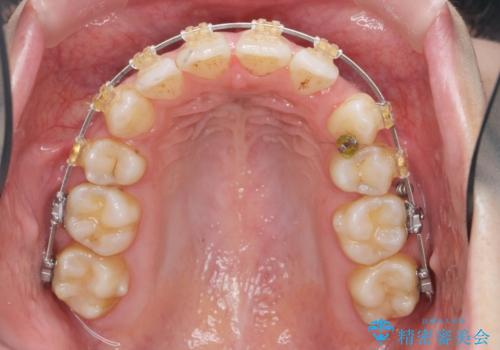

- ワイヤー矯正

- 3年

- 10-30回

- 唇の閉じづらさと、前歯のがたつきの改善を希望され来院されました。

抜歯を行わなくてもなんとか並べられる歯並びですが、唇の閉じづらさをしっかりと改善するため抜歯を伴うマルチブラケット矯正を行うこととしました。